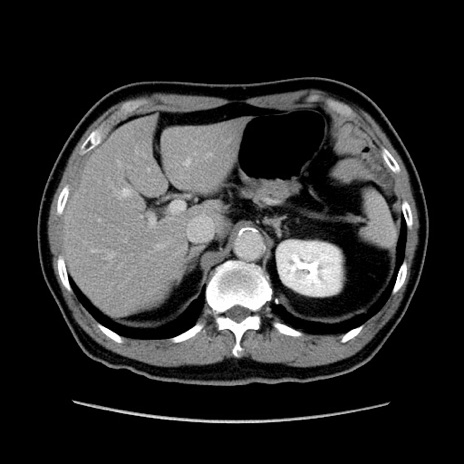

矢状断像